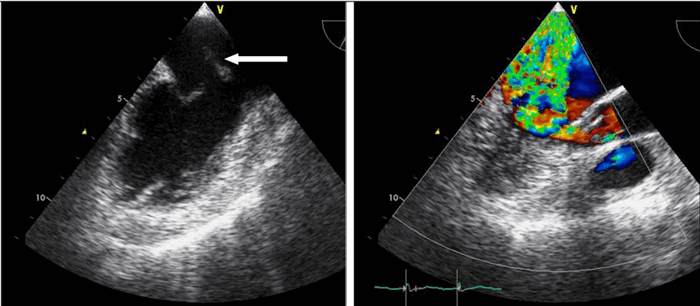

Цветовой допплер (Color Doppler). Цветовой допплер - аналог импульсного допплера, где направление и скорость кровотока картируется различным цветом. Так кровоток к датчику принято картировать красным цветом, от датчика - синим цветом. Турбулентный кровоток картируется сине-зелено-желтым цветом.

Цветовой M-модальный допплер (Color M-mode). Сопоставление M-модального режима и цветового допплера при проведении курсора через ту или иную плоскость, позволяет разобраться в фазами сердечного цикла и патологическим кровотоком.

Тканевый допплер (Tissue Velocity Imaging). Принцип данного метода основан на картировании направления движения тканей определенным цветом. Таким образом красным цветом обозначают движение к датчику, синим - от датчика. Изучая направления движения стенок левого и правого желудочков в систолу и диастолу с помощью TVI можно обнаружить скрытые зоны нарушения локальной сократимости. Совмещение двухмерного исследования в режиме TVI с M-модальным увеличивает точность диагностики.